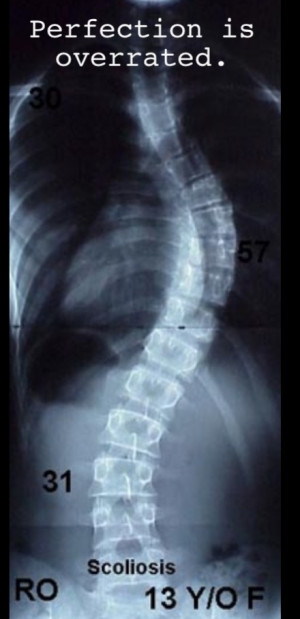

5d4e7c87ffda9fb2098a34ce99de99a2.jpg

scoliosis

Bent but Not Broken. So Why Does Conventional Treatment of Scoliosis ...